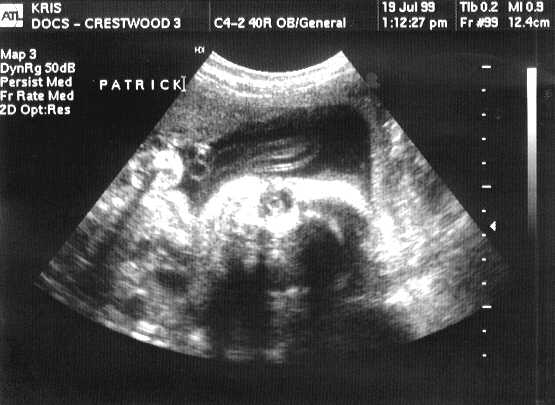

This is PATRICK JOSEPH.